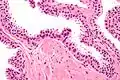

Néoplasie prostatique intraéphithéliale de haut grade (HGPIN)